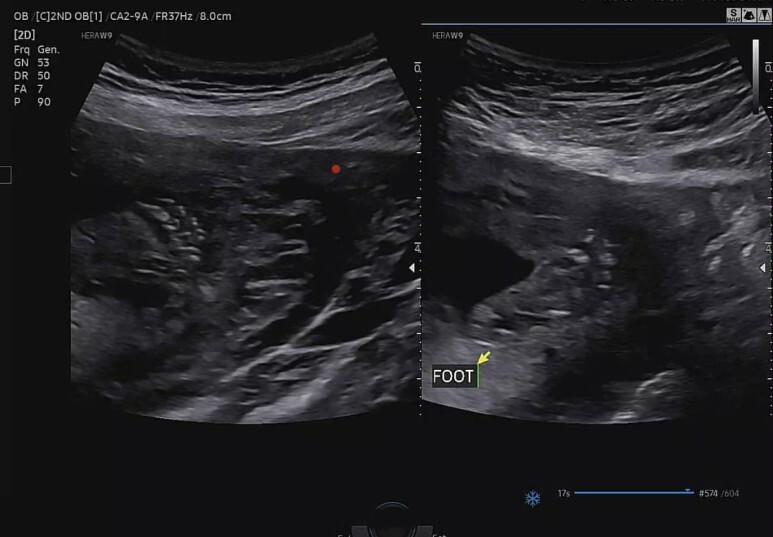

양 발가락 확인 (FOOT)

꿀잠이가 왼쪽 발을 자꾸 꼬고 엄마 배꼽 뒤로 숨고 안보여줘서 한~참을 찾아 헤맸다.